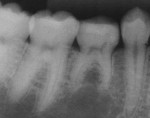

Fourteen months later, the ACTIVA Restorative platform had virtually identical contact with the opposing premolar. In addition, there was no evidence of wear or marginal chipping or staining (Figure 8 and Figure 9) and the root structure was sound with no evidence of resorption (Figure 10 and Figure 11).